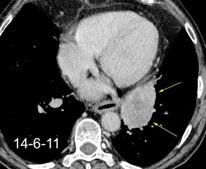

Síndrome de afectación postcardiaca (postcardiac injury)

Post infarto 1-7 % (Dressler)

Trauma cerrado Implantación marcapasos

Cirugía cardiaca. 17-31% (Post.pericardiotomía)

3707 pacientes 29 Derrames (0,78%) > de 25% del hemitórax

Todas menos 2 Izdos.

Angioplastia

By-pass coronario 21-10-03